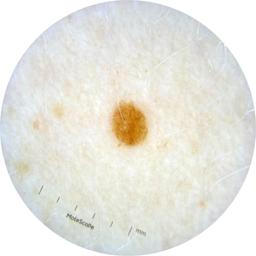

ISIC_2261268

2061 x 2061

Clinical

Field Value

acquisition_day 307

age_approx 50

anatom_site_1 Trunk

anatom_site_2 Posterior trunk

anatom_site_general posterior torso

concomitant_biopsy False

diagnosis_1 Benign

diagnosis_confirm_type single image expert consensus

family_hx_mm False

fitzpatrick_skin_type I

image_manipulation instrument only

image_type dermoscopic

lesion_id IL_8976478

patient_id IP_9156603

personal_hx_mm True

sex female